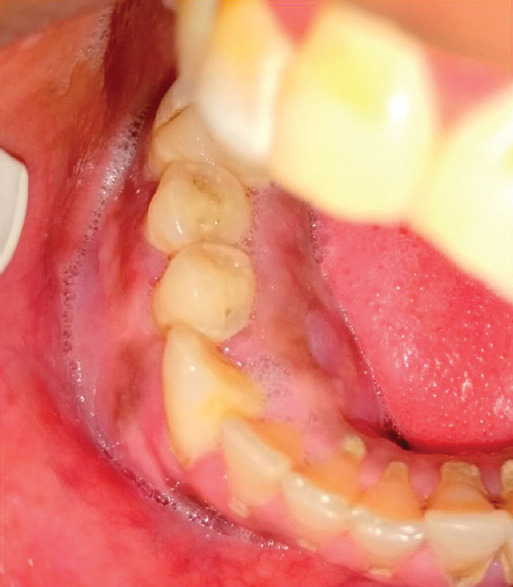

Myotonic dystrophy, also referred myotonic muscular dystrophy, is an autosomal dominant, slowly progressive, multisystem disease characterized by skeletal muscle weakness, wasting, and myotonia. A hybrid tumor of odontogenic apparatus is a lesion showing combined histopathological characteristics of two or more previously recognized odontogenic tumors and/or cysts of different categories. We, therefore, report a case of hybrid tumor (adenomatoid odontogenic tumor associated with calcifying cystic odontogenic tumor) in a myotonic dystrophic patient.